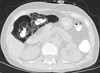

Imaging findings of pneumatosis intestinalis posttransplant are unique as compared to PI seen in other scenarios such as bowel ischemia. PI in posttransplant patients has a bubble-like/expansile appearance with a significant amount of air within the bowel wall (Figures 1 and 2). In these patients, it is helpful to view the pneumatosis on lung windows in order to properly assess its extent (Figure 3). In contrast, for PI in a patient with intestinal ischemia (Figure 4), imaging findings show more of a thin rim of gas bubbles within the submucosa without the expansile appearance. Although posttransplant PI can appear as a thin layer of gas, it would be unusual for intestinal ischemia to appear as bubble-like/expansile. Thus, if the bubble-like/expansive appearance of PI is seen, it may support a benign etiology and clinical course.